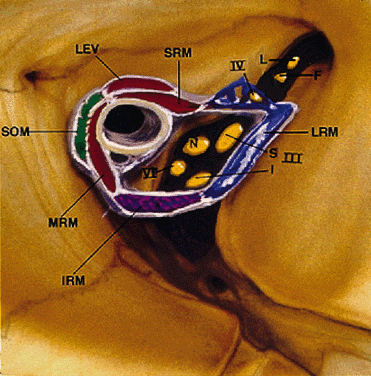

The annulus of Zinn represents a complex, dense, fibrous band of connective tissue with firm attachments to the periosteum of the orbital apex (Fig. 12). Medially, it is fused to the optic nerve sheath, which may account for the pain during eye movements experienced by patients with optic neuritis. All four rectus muscles arise directly from the annulus. Conversely, the levator and superior oblique muscles are not attached to the annulus, arising instead above the superior rectus muscle and the lesser wing/body of the sphenoid, respectively (Table 6). The final EOM, the inferior oblique, begins lateral to the nasolacrimal duct ostium in the anterior orbit.

Fig. 12. Annulus of Zinn. III-S, superior division of oculomotor nerve; III-I, inferior division of oculomotor nerve; IV, trochlear nerve; VI, abducens nerve; L, lacrimal nerve; F, frontal nerve; N, nasociliary nerve; SRM, superior rectus muscle; LEV, levator palpebris superioris muscle; SOM, superior oblique muscle; MRM, medial rectus muscle; IRM, inferior rectus muscle; LRM, lateral rectus muscle. (Modified from Zide BM, Jelks GW: Surgical Anatomy of the Orbit, p 8. New York, Raven Press, 1985)